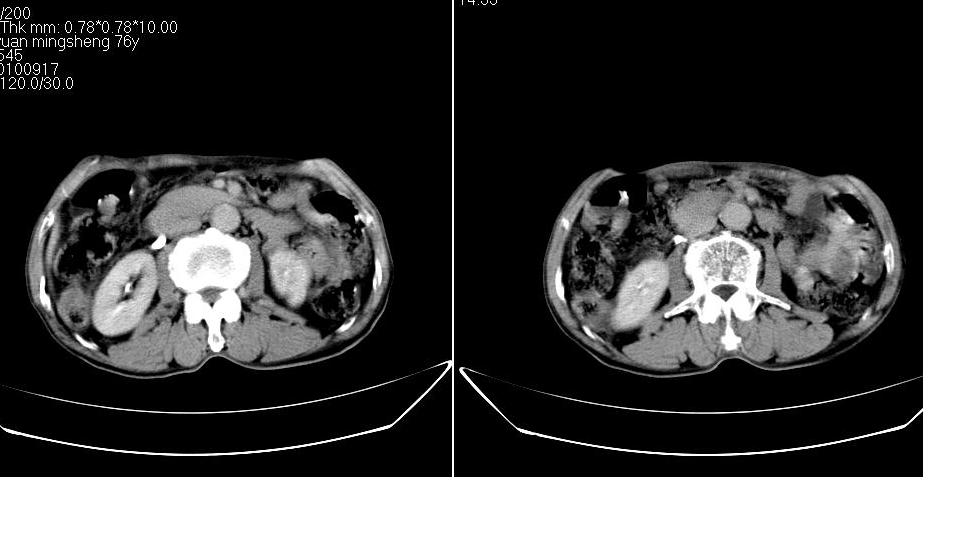

男,76岁,上腹部疼二天来就诊,彩超提示肝左叶占位,随后做上腹部ct平扫,今天做上腹部ct增强扫描,手工推药,效果不好,请谅解。

肝左叶s4肿块强化形式大概是:慢进慢出,逐渐强化----考虑血管瘤/腺瘤?{动脉期应更提前扫}。

1)肝右叶前段低密度灶,不排除肝癌可能;建议查afp。2)右肾上极囊肿。

肝内胆管积气扩张,胆囊增大,肝右前叶低密度灶,逐渐强化,一元论,胆系感染,局限性肝脓肿;右肾囊肿。

考虑肝s4段肝脓肿可能?未排除肝癌。右肾上极囊肿。